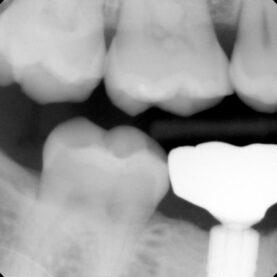

As the crown was still in place and noting from the intake form the abutment was from Atlantis, which like the OEM Ankylos abutments, has a free-floating laser assembled screw as the screw threads at M1.8 are larger than the through bore diameter of the abutment, 1.12mm. Therefore, the easiest way to access the implant top is to cut the head of the abutment screw off which releases the crown. The following preop. photo was taken at this point in the recovery. The photo on the right shows the edentulous space for a greater understanding of the thin fractured abutment cross section relative to the large mesial to distal space. This visually demonstrates the amount of mesial-distal space which translates into a huge amount of applied torsional loading onto the thin fractured cross section.

The abutment recovery was routine with reduction of the abutment screw down 3mm to expose the through bore. Next the through bore was tapped to M1.6mm, the distractor bolt was threaded into place and followed by placement of the distractor nut. The fractured conical portion of the abutment was then distracted and recovered. With microscope guidance, the remaining mobile abutment screw fragment was carefully rotated clear of the implant threads and recovered. The implant was cleaned, and the supplied healing abutment was placed finger tight. There was no visible implant damage when examined at 25x magnification. She was referred back to Dr. W. for treatment planning and future restoration.